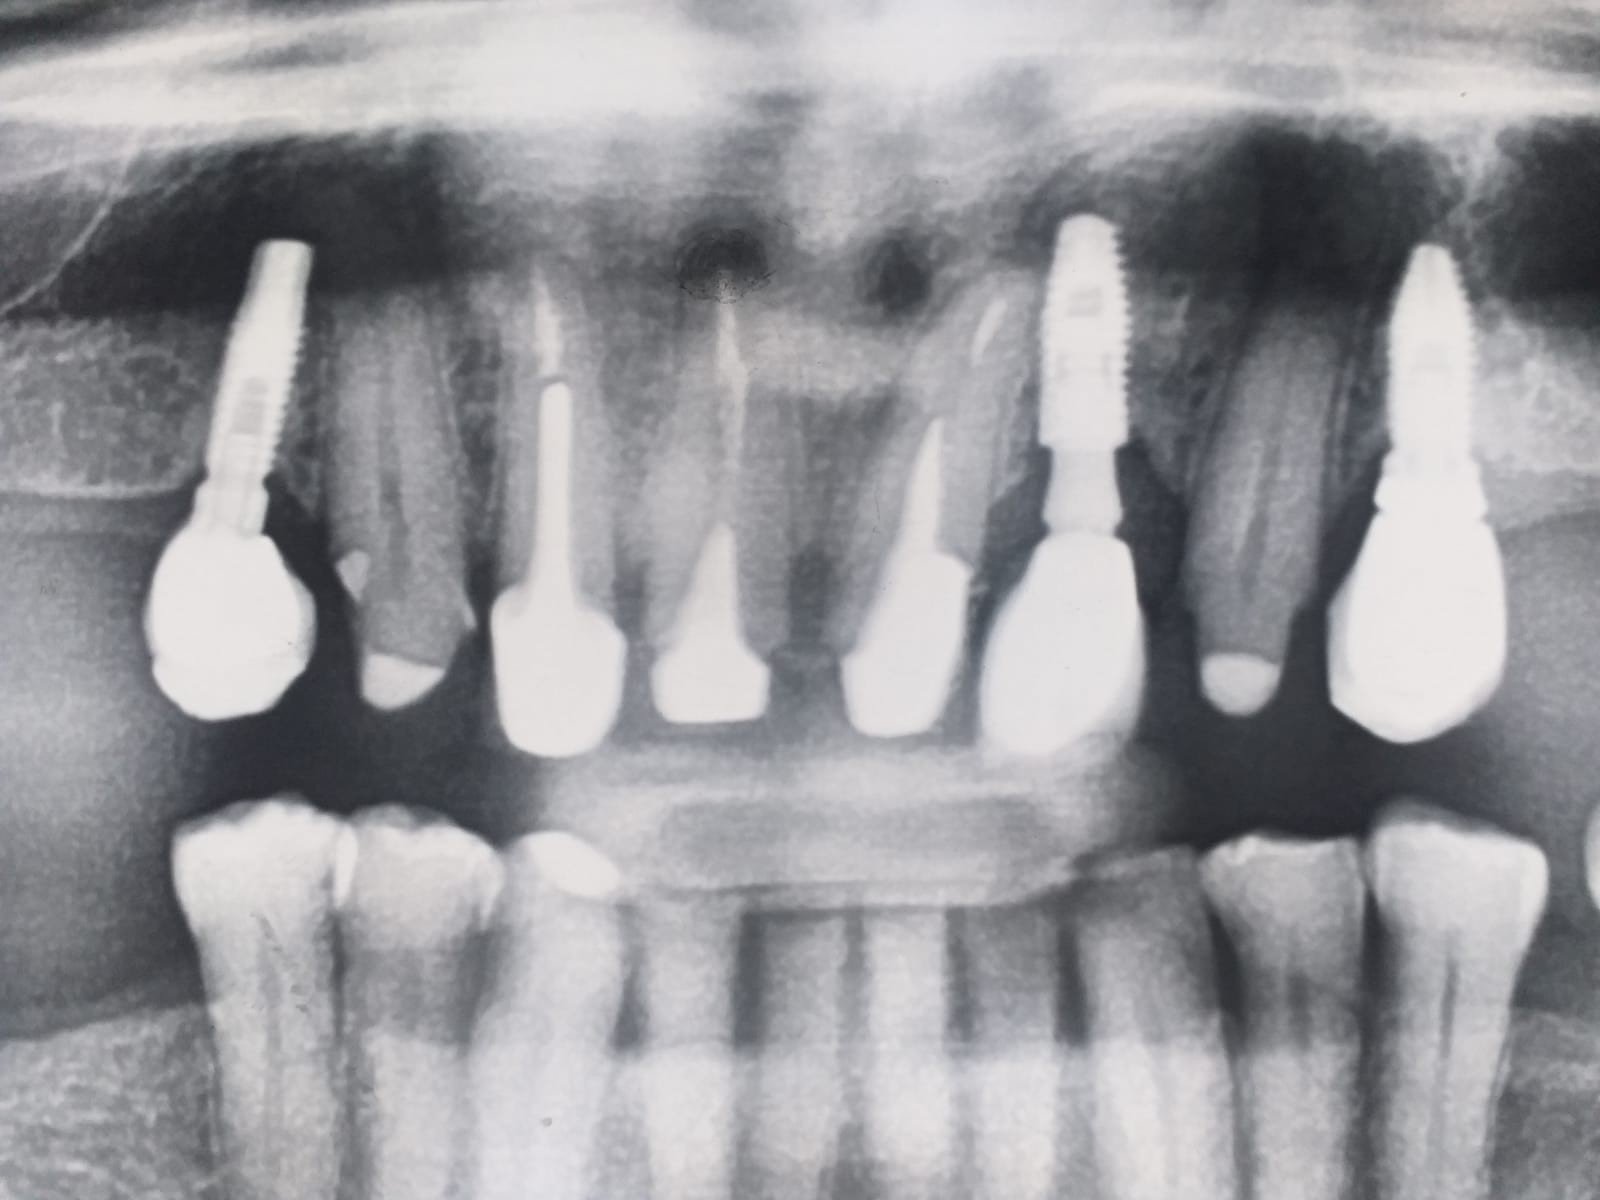

Porfavor, podrían ayudarme a identificar los tres implantes de la radiografía. ¿Que conexión tienen?. ¿Que aditamento de protesis necesitaría para poder rehabilitar los? Gracias

El implante de la izquierda no sé de que marca puede tratarse y q conexión y si es compatible con alguna otra.el 22 es un 3i conexion interna de 3.25.muchas [...]